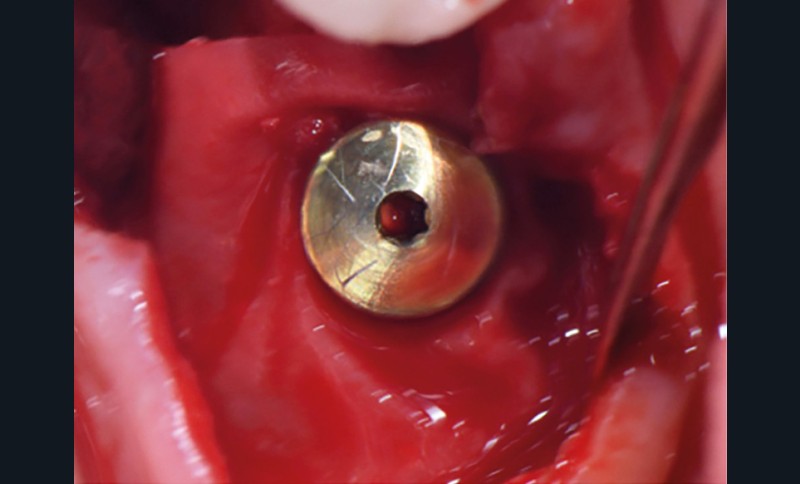

L’implant

- Péri-implantite sur l’implant 47, diagnostiquée en août 2022

- Poches de 6 à 7 mm

- Implant posé en 2017

- Nobel Replace Select RP (4,1 x 10 mm)

La couronne a été déposée et une vis de couverture mise en place. La patiente a reçu un nettoyage supra-gingival général avec une attention particulière pour l’implant 47, et une irrigation locale avec du gel de chlorhexidine et du peroxyde d’hydrogène pour réduire l’inflammation des tissus. De l’amoxicilline (3 x 500 mg) a été prescrite, à commencer la veille de l’intervention chirurgicale.